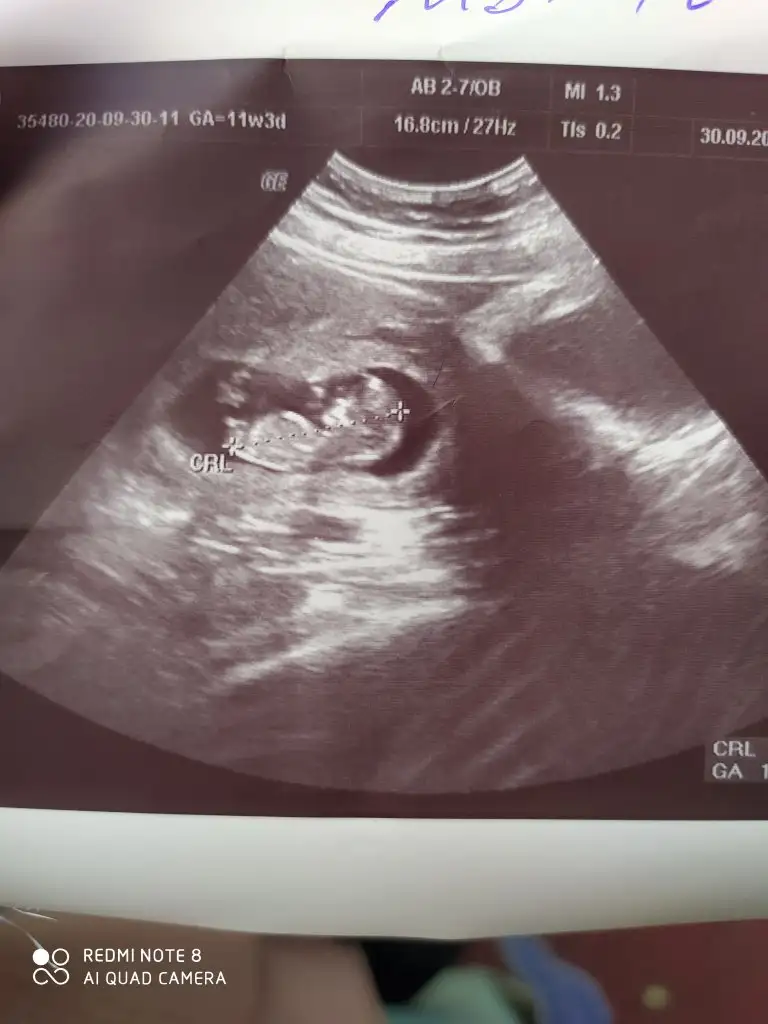

12+4 arkadaşlar anlayan yorum yapabilir mi acaba?

Aynı bizim oğlan gibi ama bilemedim sağlıklı olsun da12+4 arkadaşlar anlayan yorum yapabilir mi acaba?

erkek canim.